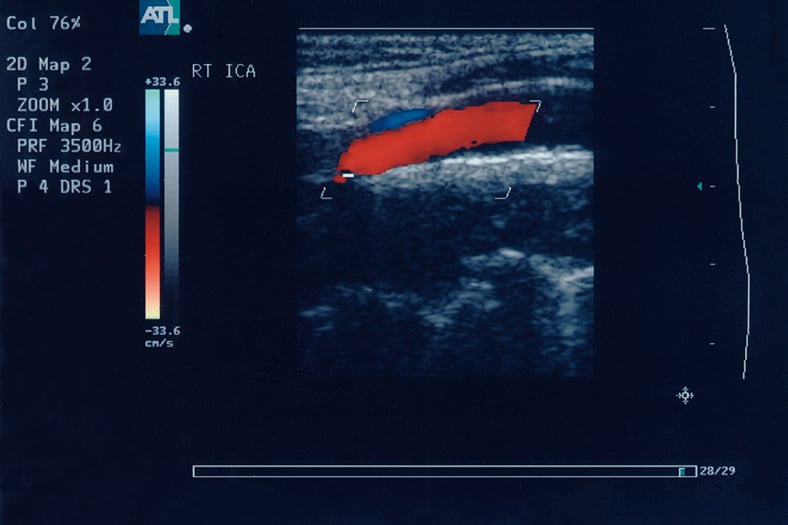

Sonography also doesn’t use medical radiation. It uses sound waves to produce an image. A transducer sends high-frequency sound waves to the area being imaged. As those sound waves bounce off organs and tissues, they send back an echo. Computer equipment converts those echoes into visual data.

Sonograph image / Image © ASRT

Sonograph image